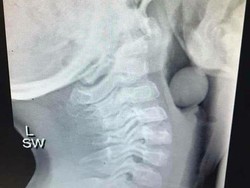

Elsa Putri Julita (20) meninggal beberapa jam sebelum melangsungkan pernikahannya dengan Darmadi (19). Dokter menyebutkan asam lambung menjadi pemicunya.